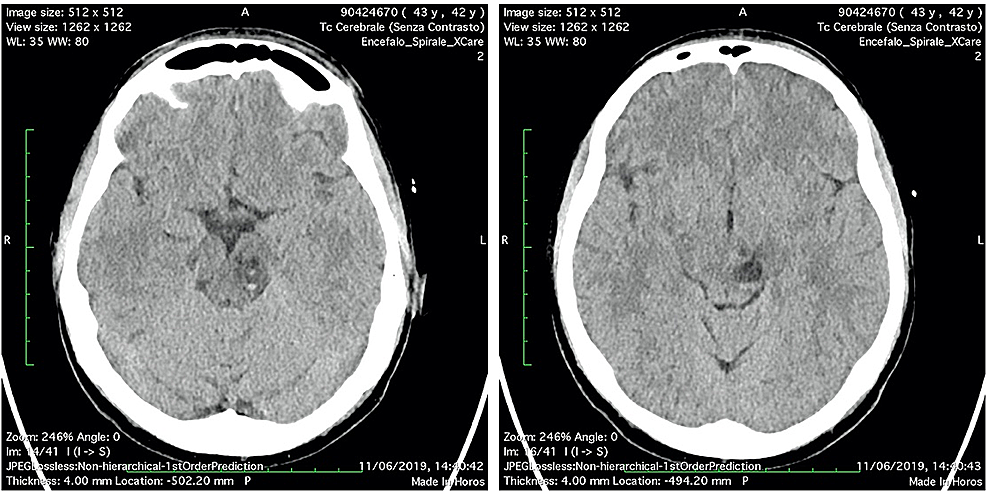

A 42-year-old woman, without previous disease, was admitted in the Emergency Room for a polytrauma during an accident car. Clinically she was conscious; she had a head trauma with hairy scalp; she complained headache and pain of the left foot; on the accident set, opiates were administered. Pressure of oxygen (PaO2) was 98%, cardiac frequency was 65 bpm, Glasgow Coma Scale was 15, and the neurological examination was negative. Laboratory tests revealed hemoglobin: 10.7 g/dL (normal range 12-16 g/dL), white blood cell: 11.71 x 109/L (normal range 4-10 x 109/L), coagulation tests in normal range, and normal platelet count. A total body CT was performed; it demonstrated, beyond the hairy scalp with large soft tissue loss in frontoparietal zone, a multiloculated cyst in the left midbrain, with eccentric hyper-density, hematic-like (Figure 1). An X-ray of the left foot showed a fracture of the first toe. In absence of neurological deficit, the patient immediately underwent surgery for the reconstruction of the scalp.